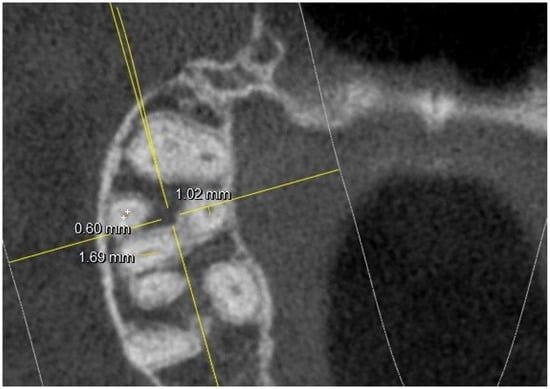

- long and short diameter of the pulp chamber floor;

- diameter of root canal orifices;

- distance between intra- and inter-root canals;

| At the orifice: M-B diameter | 0.65 | 0.21 | 0.81 | 0.17 | 0.74 | 0.24 | 0.67 | 0.21 | ||

| D-B diameter | 0.69 | 0.11(2 NO) | 0.72 | 0.14 (1 NO) | 0.65 | 0.12 (1 NO) | 0.69 | 0.15 (3 NO) | ||

| Palatal diameter | 0.89 | 0.18 | 0.89 | 0.21 | 1.12 | 0.16 | 0.89 | 0.18 | ||

| Mb2 diameter | 0.38 | 0.12 (6 NO) | 0.3 | 0.8 (10 NO) | 0.39 | 0.9 (3 NO) | 0.34 | 0.8 (15 NO) | ||

| At the orifice: MB-DB distance | 2.33 | 0.22 | 2.35 | 0.21 | 2.22 | 0.2 | 2.19 | 0.2 | ||

| DB-P distance | 2.96 | 0.44 | 3.25 | 0.2 | 3.32 | 0.41 | 3.67 | 0.2 | ||

| P-MB2 distance | 3.65 | 0.52 | 3.39 | 0.42 | 3.62 | 0.48 | 3.68 | 0.39 | ||

| MB1-MB2 distance | 1.54 | 0.21 | 1.67 | 0.21 | 1.63 | 0.19 | 1.45 | 0.22 | ||

| MB-P distance | 4.91 | 0.3 | 5.03 | 0.36 | 5.02 | 0.26 | 4.87 | 0.31 | ||